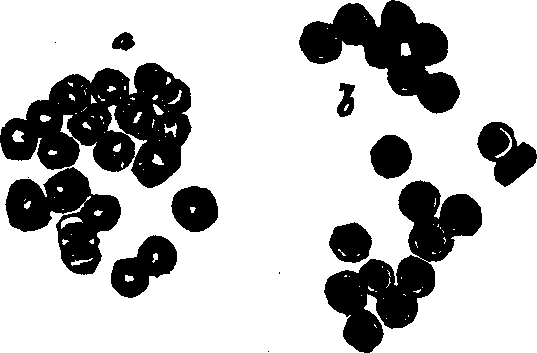

Fig. 38. Red corpuscles of human blood, represented at

a, as they are seen when rather beyond the focus of the

microscope; and at b as they appear when, within the focus.

Magnified 400 diameters.

Fig. 39.

Development of human lymph and chyle-corpuscles into red corpuscles of

blood. A. A lymph, or white blood-corpuscle. B. The same in

process of conversion into a red corpuscle. C. A lymph-corpuscle

with the cell-wall raised up around it by the action of water. D. A

lymph-corpuscle, from which the granules have almost disappeared. E.

A lymph-corpuscle, acquiring color; a single granule, like a nucleus,

remains. F. A red corpuscle fully developed.